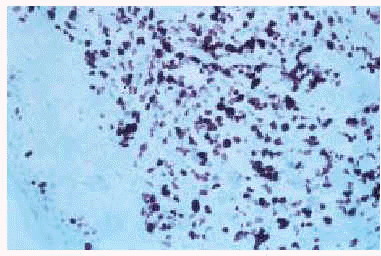

El estudio histológico de las lesiones, tanto de los nódulos como de las maculopápulas, ponía de manifiesto la existencia, bajo una epidermis normal, de un denso infiltrado que ocupaba desde dermis media hasta hipodermis respetando una fina banda superficial (fig. 3). El infiltrado era monomorfo y estaba formado por células de citoplasma escaso y núcleos irregulares con abundantes mitosis (fig. 4). En el estudio inmunohistoquímico se evidenciaba que dichas células pertenecían a la serie monocito-histiocitaria (CD43+, CD68+, CD15+) (fig. 5), con índice proliferativo muy alto (fig. 6).

Fig. 5.--Positividad del infiltrado para la tinción con CD43.